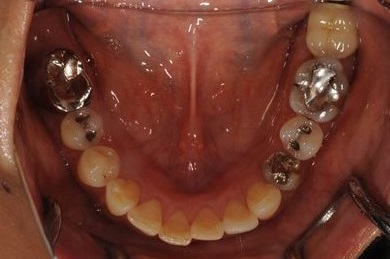

インプラントの症例写真 IMPLANT

骨再生インプラント治療+セラミック治療+歯肉歯槽骨整形

| 性別/年齢 | 女性 / 42歳 | ||||||||||||||||||||||||||||||||

| 主訴 | インプラント治療を受けたい。 | ||||||||||||||||||||||||||||||||

| 治療方針 | 左上奥欠損部分をインプラント治療にて機能的・審美的回復を行う。 | ||||||||||||||||||||||||||||||||

| 治療内容 | インプラント2本(ソケットリフト)、メタルボンドセラミック3本(メタルボンド用土台1本)、歯肉歯槽骨整形 | ||||||||||||||||||||||||||||||||

| 総治療費 | 1,227,713円 | ||||||||||||||||||||||||||||||||

| 治療期間 | 11ヶ月 |